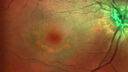

78 year old female No visual complaints referred for evaluation

Medical Hx: Rheumatoid Arthritis. Atrial Fibrillation. Benign Intracranial Hypertension. Sjogrens Syndrome. Osteoporosis.

Systemic Meds: PLAQUENIL (Stopped 2 months ago). Leflunomide. Lidocaine. Gabapentin. Vitamin D. Multaq. DILTIAZEM.

1993 Plaquenil Initially 400 mg /day (9 mg/kg/day x 18 years) then 2011 200 mg daily - (4.6 mg/kg/day x 10 years) STOPPED 3/2021

The patient weighs 100 lbs and is 4’ 2†tall - Images are from 3/2021 and 5/2022

There was no progression 1 year after stopping plaquenil in this patient.